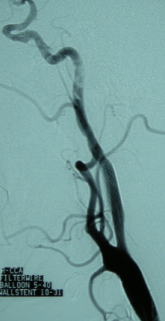

血管狭窄时脑卒中的独立危险因素,近年来开展的血管内支架植入术对治疗颅内外动脉狭窄,预防卒中复发具有重要意义。我科术前充分进行风险-效益评估,严格把握手术适应证。先通过脑血管造影明确是否存在血管狭窄、动脉瘤等解剖异常,动态、全面地观察脑血管血流情况、变异情况、侧支代偿情况、Willis环情况和计算狭窄率,根据造影结果了解血管内支架植入术的路径、选择合适类型的支架和规格,然后择期手术。动脉支架放置术与颈动脉内膜剥脱术比较具有创伤小,手术并发症低等特点,可在局部麻醉下进行,手术病人所受的痛苦及住院天数均较少,心脏血管并发症极低,减少中风之效果甚佳,支架置入术的有效率达95%,合并症小于5%。由于其微创、操作安全性高以及并发症较少,目前我科技术日渐成熟,使越来越多的患者受益。

植入前

植入后